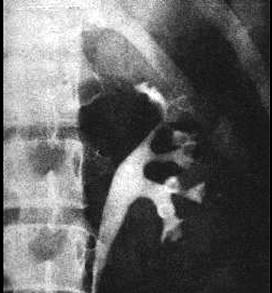

问题 排泄性或逆行性肾盂造影,有下列哪种表现为早期肾结核 ( )

选项 A、肾盂肾盏模糊变形 B、肾内有斑点状钙化影 C、肾盏边缘不整齐,如虫蛀样改变 D、肾盂肾盏不规则扩大 E、肾盏闭塞,空洞形成

答案 C